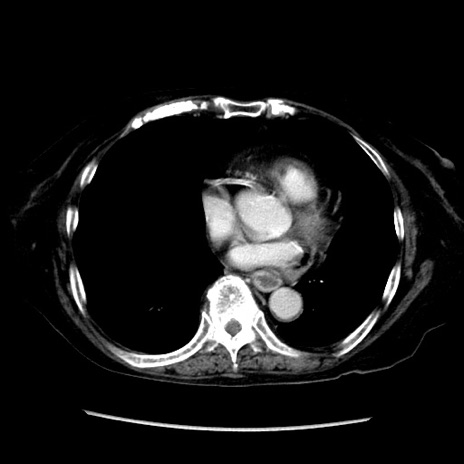

症例14(横断像)

【症例】 90歳代女性

【主訴】 腹痛・嘔吐

【現病歴】今朝から左側腹部痛を認めた。 経過観察していたが、嘔吐を認めたため来院。

【既往歴】 子宮癌術後

【身体所見】 意識清明、BP 127/54mmHg、P 98bpm Sp02 95%(RA)、BT 35.8°C、腹部平坦・軟腸ぜん動音聴取良好、右下腹部圧痛(+) 反跳痛なし

【データ】WBC 9800、CRP 0.46